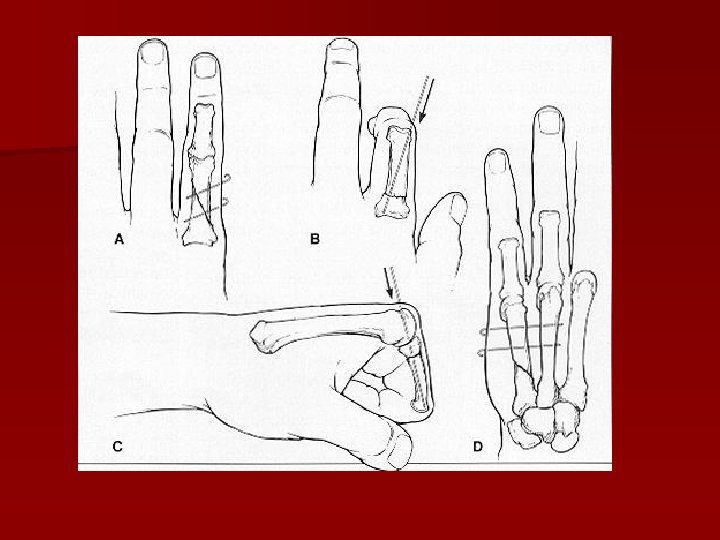

Osteosinteză centromedulară